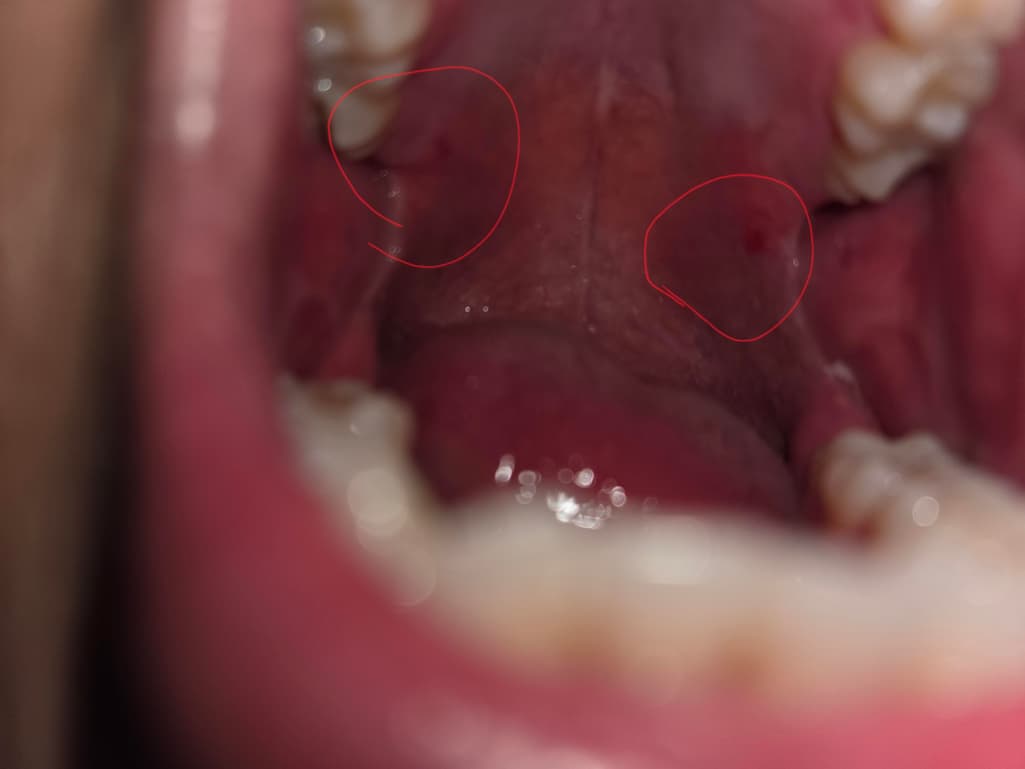

방금 저녁으로 치킨 순살을 먹고 화장실에서 손을 씻고 가래를 뱉었는데 피가 나와서 처음에는 양념치킨의 양념인줄 알았습니다.

혹시나 해서 스마트폰 플래쉬로 확인하니 사진처럼 두 군데가 까졌고 그중 한 군데에서 피가 뱉을때마다 나오네요...

말하신 내용 답변 드리자면 사실 치킨의 양념이나 섬유질이 있는 고기 조각이 입천장이나 편도에 자극을 줄 수 있어서, 이를 물어먹거나 씹을 때 가벼운 찰과상이나 작은 상처가 생길 수 있습니다. 이로 인해 피가 나는 것일 가능성이 큽니다.

편도가 까졌다고 하셨는데, 이는 일시적인 찰과상일 수 있으며, 특별한 치료 없이 자연히 회복될 가능성이 높습니다. 다만, 만약 상처 부위에서 피가 계속 나오거나, 통증이 심해지거나, 부종이 생긴다면 감염의 징후일 수 있으므로 병원을 방문하여 치료를 받는 것이 좋아요